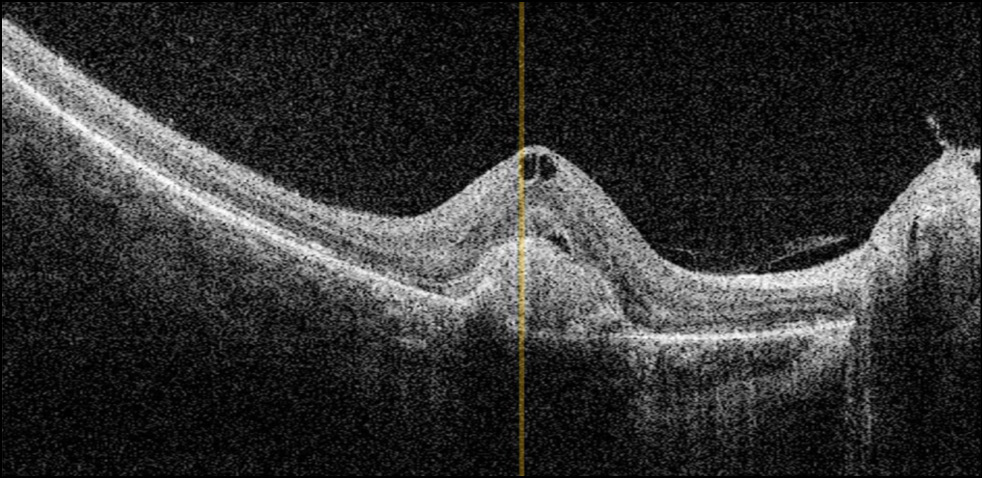

In this study, 41 children (48 eyes, 78.7%) had type 2 CNM localized between the pigment epithelium and neurosensory retina (Fig. 5). In addition, 13 children (13 eyes) had type 1 CNM developing under the pigment epithelium (Fig. 6). No correlation was established between the CNM type and underlying disease. Type 1 was diagnosed in six children with inflammatory lesions of the retina and choroid with varying activity and localizations and in seven children with congenital and acquired retinal and optic nerve pathologies of noninflammatory genesis.

Fig. 5. Optical coherence tomography (OCT) image of choroidal neovascularization type 2 in a child with toxoplasmosis retinochoroiditis in remission.

Fig. 6. Optical coherence tomography (OCT) image of choroidal neovascularization type 1 in a child with chorioretinitis of unclear etiology in remission.